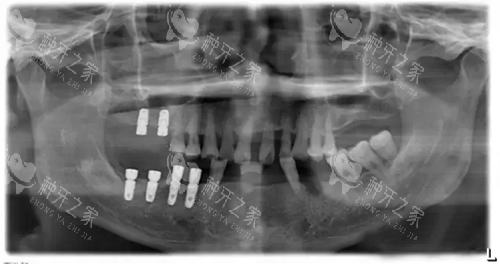

韩国美格真种植体X光片.webp

在技术方面,韶南口腔医院也有自己的优势。

其手术室配置了三维影像设备,能立体呈现牙槽神经走向,为种牙手术提供了更更准一些的依据。